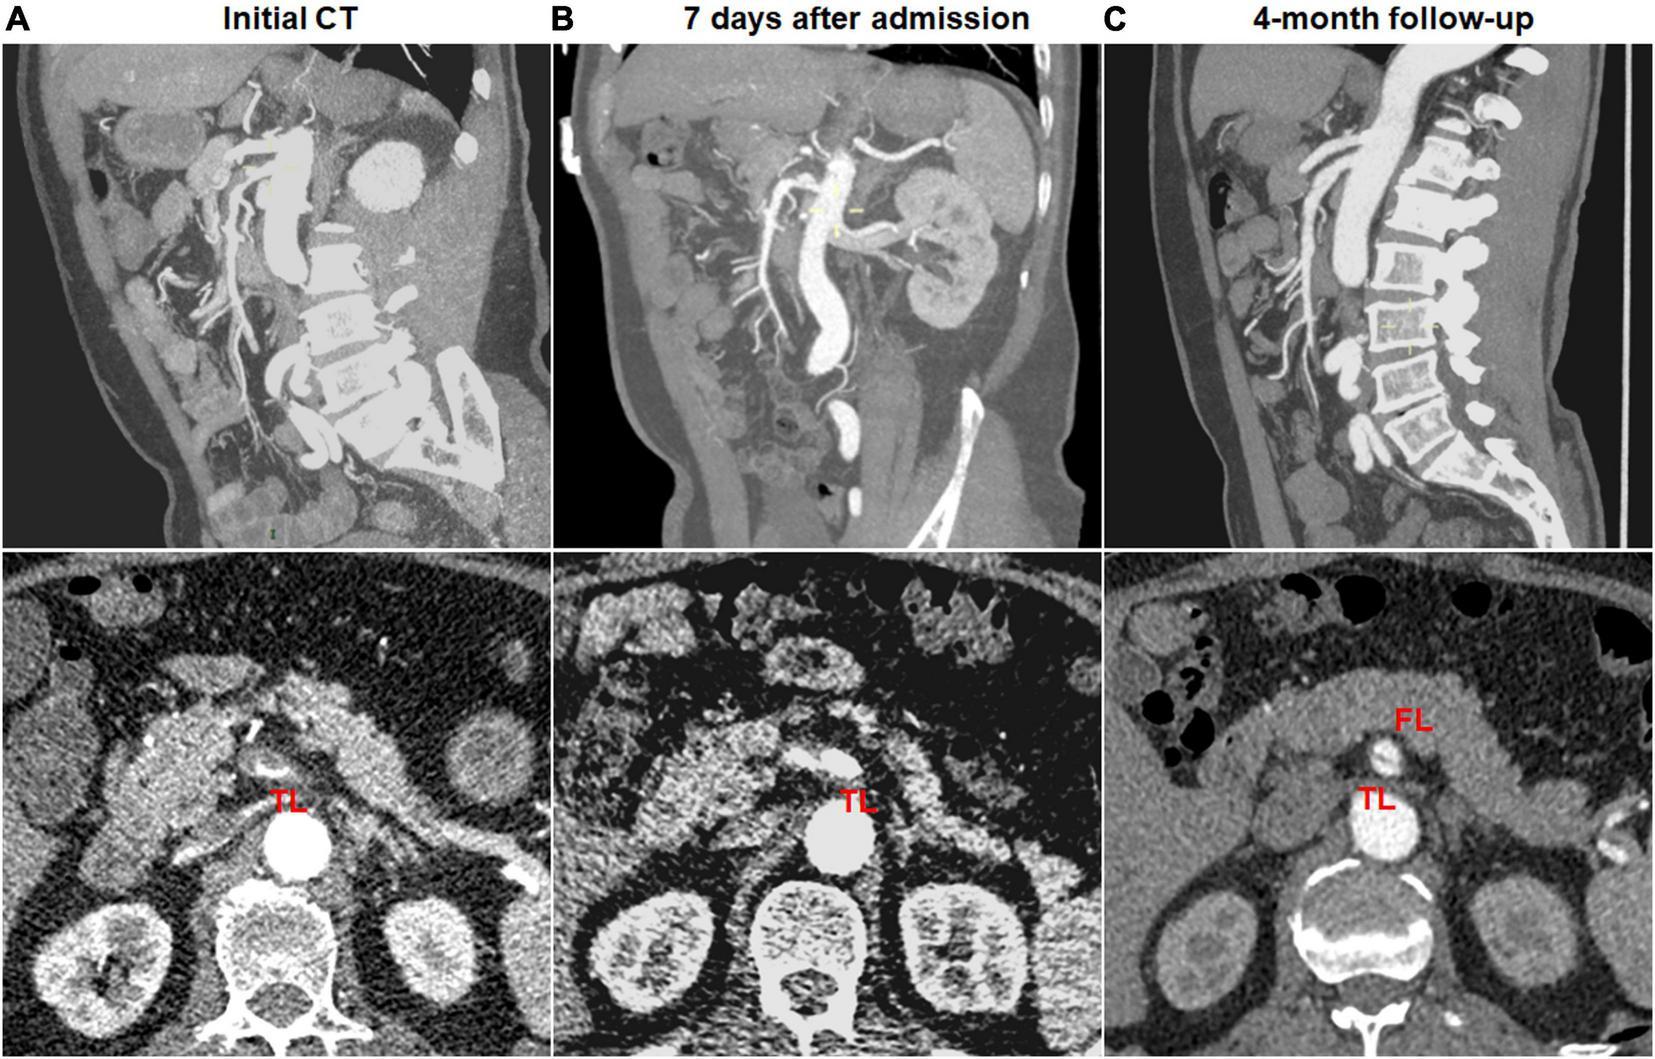

Type change on CTA was noted in 10 (41.7%) of 24 type III dissections of thrombosed FL with ULP and 2 (12.5%) of 16 type IV dissections of the completely thrombosed FL. 10 type III lesions evolved into type II dissections of “cul-de-sac” shaped FL without re-entry (Figure 7), and the stenosis of TL was improved with hematoma regression. The mean diameter of TL increased from 3.6 ± 1.2 mm on initial CT to 5.9 ± 1.3 mm on follow-up CT (p = 0.001). 1 type III lesion developed into type II with TL severely compressed and received stent assisted coiling (Figure 1).

FIGURE 7

Type change of type III spontaneous isolated superior mesenteric artery dissection on follow-up computed tomography (CT) angiography. (A) Initial CT angiography showed the thrombosed false lumen with ulcer-like projection (ULP) in a 49-year-old man. (B) One week after conservative management, the thrombosis of false lumen was partially resolved and true lumen was slightly dilated. (C) Follow-up angiogram at 4 months after conservative treatment showed double-lumen sign on an axial view and a patent “cul-de-sac” shaped false lumen without re-entry on a sagittal view (type II dissection).